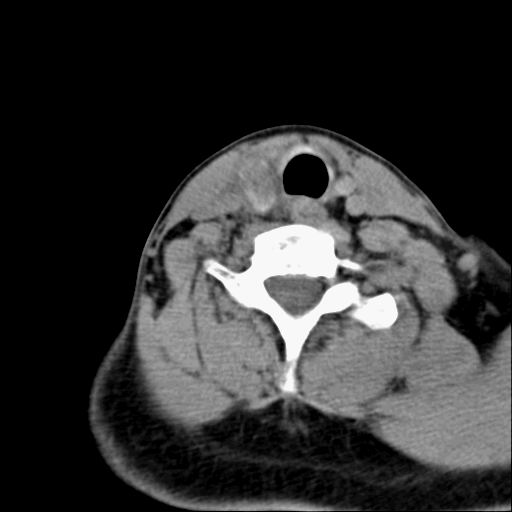

标题: CT23947 右颈部触及00.5x1.5cm质硬长形肿块,疼痛 [打印本页]

标题: CT23947 右颈部触及00.5x1.5cm质硬长形肿块,疼痛

右侧甲状腺腺瘤考虑

甲状腺癌可疑

右侧甲状腺病灶,建议增强或结合b超检查。

右甲状腺占位,建议增强。

甲状腺腺瘤或癌